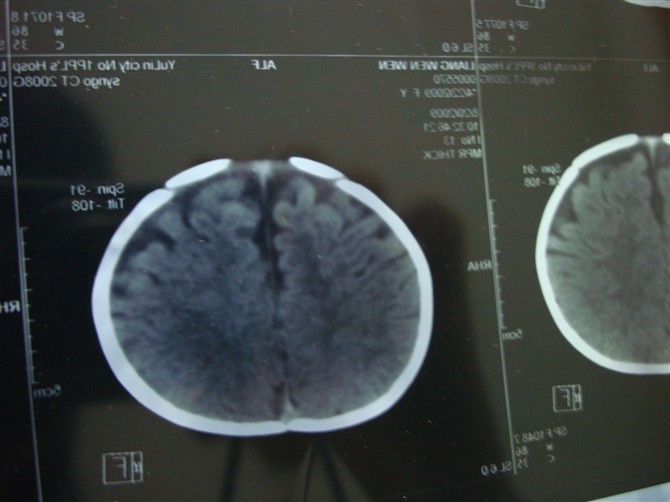

朋友的女儿,被玉林市第一人民医院医院诊断脑积水,各位老师帮忙看下!

顺产,无缺氧史,经常哭闹,无其它不适!

胼胝体发育不良,外部性脑积水。脑白质密度减低,hie后遗症?

外部性脑积水,在第四军医大出版的《小儿ct诊断图谱中》诊断标准。书中列举四条标准:1。额顶部颅壁下间隙增宽在6-10mm;2。前纵裂增宽;3。脑室可增大或表现正常;4。属自限性疾病,1岁半以后可表现正常。 现在叫脑外间隙增宽 外部性脑积水国外文献又称其为 “假性脑积水”。临床可分为特发性外部性脑积水和继发性外部性脑积水。

1.特发性外部性脑积水 表现为不明原因的抽搐或(和)头围异常增大,ct改变符合外部性脑积水特征。特发性外部性脑积水原因还尚不清楚,可能与蛛网膜颗粒的发育滞后、发育不全或功能低下有关。

2.继发性外部性脑积水 继发于脑缺氧、硬膜下血肿、脑室出血、蛛网膜下腔出血、脑膜炎以及颅脑外伤后具备上述特征者。

特发性外部性脑积水的发病机理目前亦不十分清楚,但多数学者认为与蛛网膜颗粒发育迟缓,吸收脑脊液的功能发生障碍有关。继发性外部性脑积水主要是因脑膜炎、脑室出血、蛛网膜下腔出血等,使蛛网膜发生粘连、肥厚、增生,形成蛛网膜机械性梗阻或炎症性改变而影响脑脊液的吸收。

图像不连续,外部性脑积水诊断问题不大,另外,三脑室上抬,侧脑室间距增宽,支持考虑胼胝体发育不良。